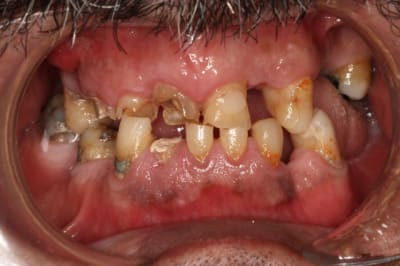

Patient vu vendredi passé...

Endo 21-11-12-13

Il reste aussi 15 et 26

Plan de tx :

Pas d'implants...pour l'instant

Couronnes 12, 11 et 26

Bridges 15-X-13 et 21-X-23

Stellite

Alors, IC ou pas sur les endo ?

13 ?

12 ?

11 ?

21 ?

Pour le bas...vendredi prochain...à suivre